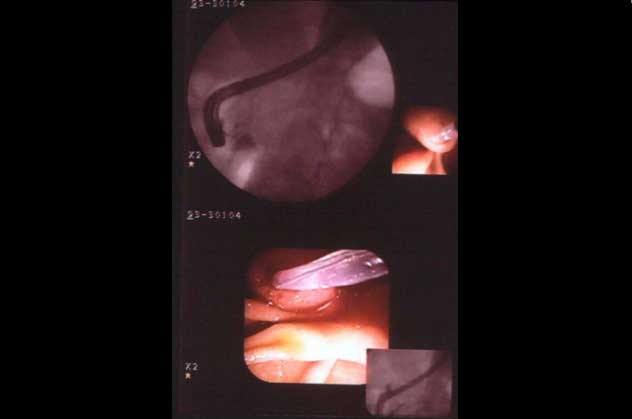

This slide shows combination of X|ray and electro|endoscopic image in one display.